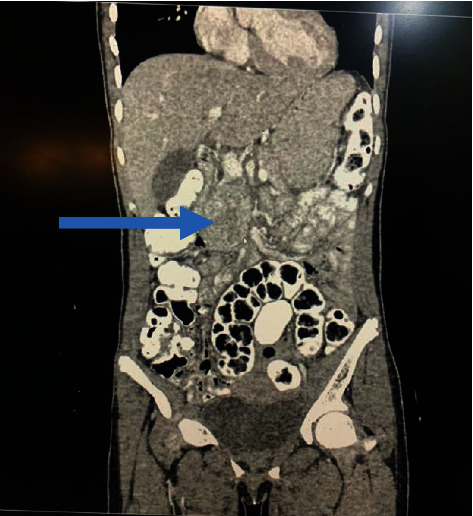

Introduction: A paraganglioma (PGL) is a tumour derived from extra-adrenal chromaffin cells of the sympathetic paravertebral ganglia of the thorax, abdomen, and pelvis. Cardiovascular manifestations predominate but neurological symptoms like seizures can occur requiring a high index of suspicion for prompt diagnosis and treatment. Case Description. A 14-year-old girl was referred to the paediatric neurology unit for recurrent headaches of one-year duration, vomiting of 2 months duration, and an episode of generalized tonic-clonic seizures, 2 weeks prior to presentation. There was an associated history of impaired vision, palpitations, diaphoresis, and easy fatigability. Her blood pressure ranged from 150/101 to 160/120 mmHg. The brain CT scan was normal. ECG showed left ventricular hypertrophy. Abdominal USS revealed a right para-aortic mass necessitating 24-hour urine normetanephrine which was markedly elevated-1695.34 mcg/24 h (100-500). An abdominal CT scan confirmed a paraganglioma in the right para-aortic region. A multidisciplinary team consisting of paediatric endocrinologists, radiologists, anaesthetists, paediatric and cardiothoracic surgeons, and the intensive care unit (ICU) team was involved in the peri and postoperative management of the child. Intraoperative challenges were hypertension and hypotension (following tumour excision). She was nursed in the ICU for 48 hours. Histology results confirmed paraganglioma. Postoperative urine normetanephrines done a month after surgery had reverted to normal. Her blood pressure has remained normal 6 months after surgery, and no other symptoms have recurred.

Abstract Image